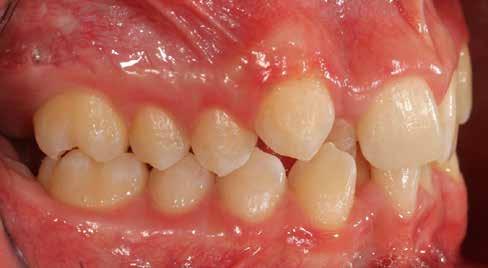

Ebben a cikkben egy 16 éves lánypáciens esetét szeretném bemutatni (1–7. képek)

Mint sok páciensem, akiknél végül nincs szükség állcsontműtétre, ők is megjárták a saját „kálváriájukat”: már több fogszabályozó kollégánál jártak, és mindegyik azt mondta nekik, hogy állcsontműtét nélkül az eset nem megoldható.

Végső elkeseredésükben időpontot foglaltak hozzám, és legnagyobb örömükre egyértelműen látszódott, hogy a Pitts Protokollok-kal nincs szükség az orthognáth műtétes beavatkozásra.

A Pitts21-es fix készülékes kezelés során a harapásemelőket a felső nagyőrlő fogakra ragasztottuk, hogy a felső molárisok intrúziójával segítsék a harapás zárását (8. kép) Ún. keresztharapásos, majd később normál class 2-es gumihúzással (9–10. képek), továbbá az elülső fogakon alkalmazott ún. Rainbow harapás-záró gumihúzással (11. kép) korrigáltuk a jobb oldali teljes premolárisnyi distal-harapást, valamint az elülső nyitott harapást.

6 hónap után a nyitott harapás már nagyjából összezárásra került (12. kép)! A gumihordás a kezelés teljes hosszában folyamatos, éjjel-nappal, 22-24 órában az étkezések és az utánuk történő fogmosás kivételével.